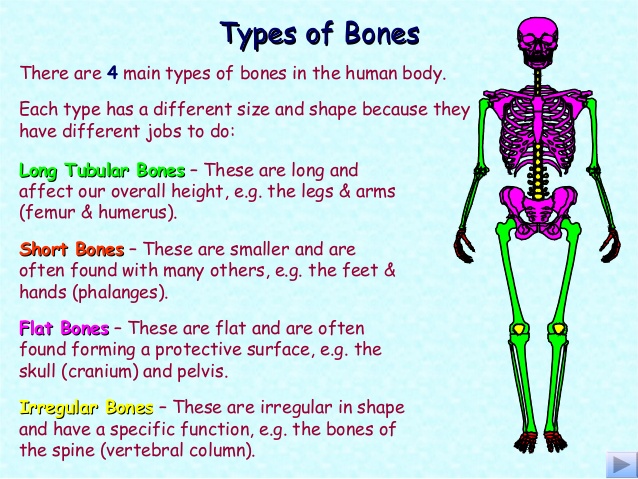

- Main bones of the skeletal system e.g. skull, humerus

The functions performed by the skeletal system in the body are as follows:

1. It allows for movement.

2. It gives shape and beauty to the body.

3. It protects the inner delicate organs of the body.

4. The skeleton gives rigidity and support the body.

5. The skeleton allows for muscle attachment.

6. The bones of the skeleton produce cells to build the blood.

7. Some of the bones act as levers for living and for carrying load.

The functions performed by the skeletal system in the body are as follows:

1. It allows for movement.

2. It gives shape and beauty to the body.

3. It protects the inner delicate organs of the body.

4. The skeleton gives rigidity and support the body.

5. The skeleton allows for muscle attachment.

6. The bones of the skeleton produce cells to build the blood.

7. Some of the bones act as levers for living and for carrying load.